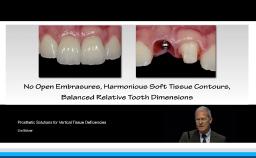

While technical advancement with mesostructures, adhesive techniques and the application of pink porcelain frequently facilitate esthetically acceptable implant restorations, implant repositioning or removal may be regarded as last resort in extreme situations.

Alternative treatment options for single-tooth replacement comprise orthodontic space closure particularly in adolescence, and adhesive restorations either with a metal framework or full ceramics as a minimally invasive temporary or long-term treatment option.